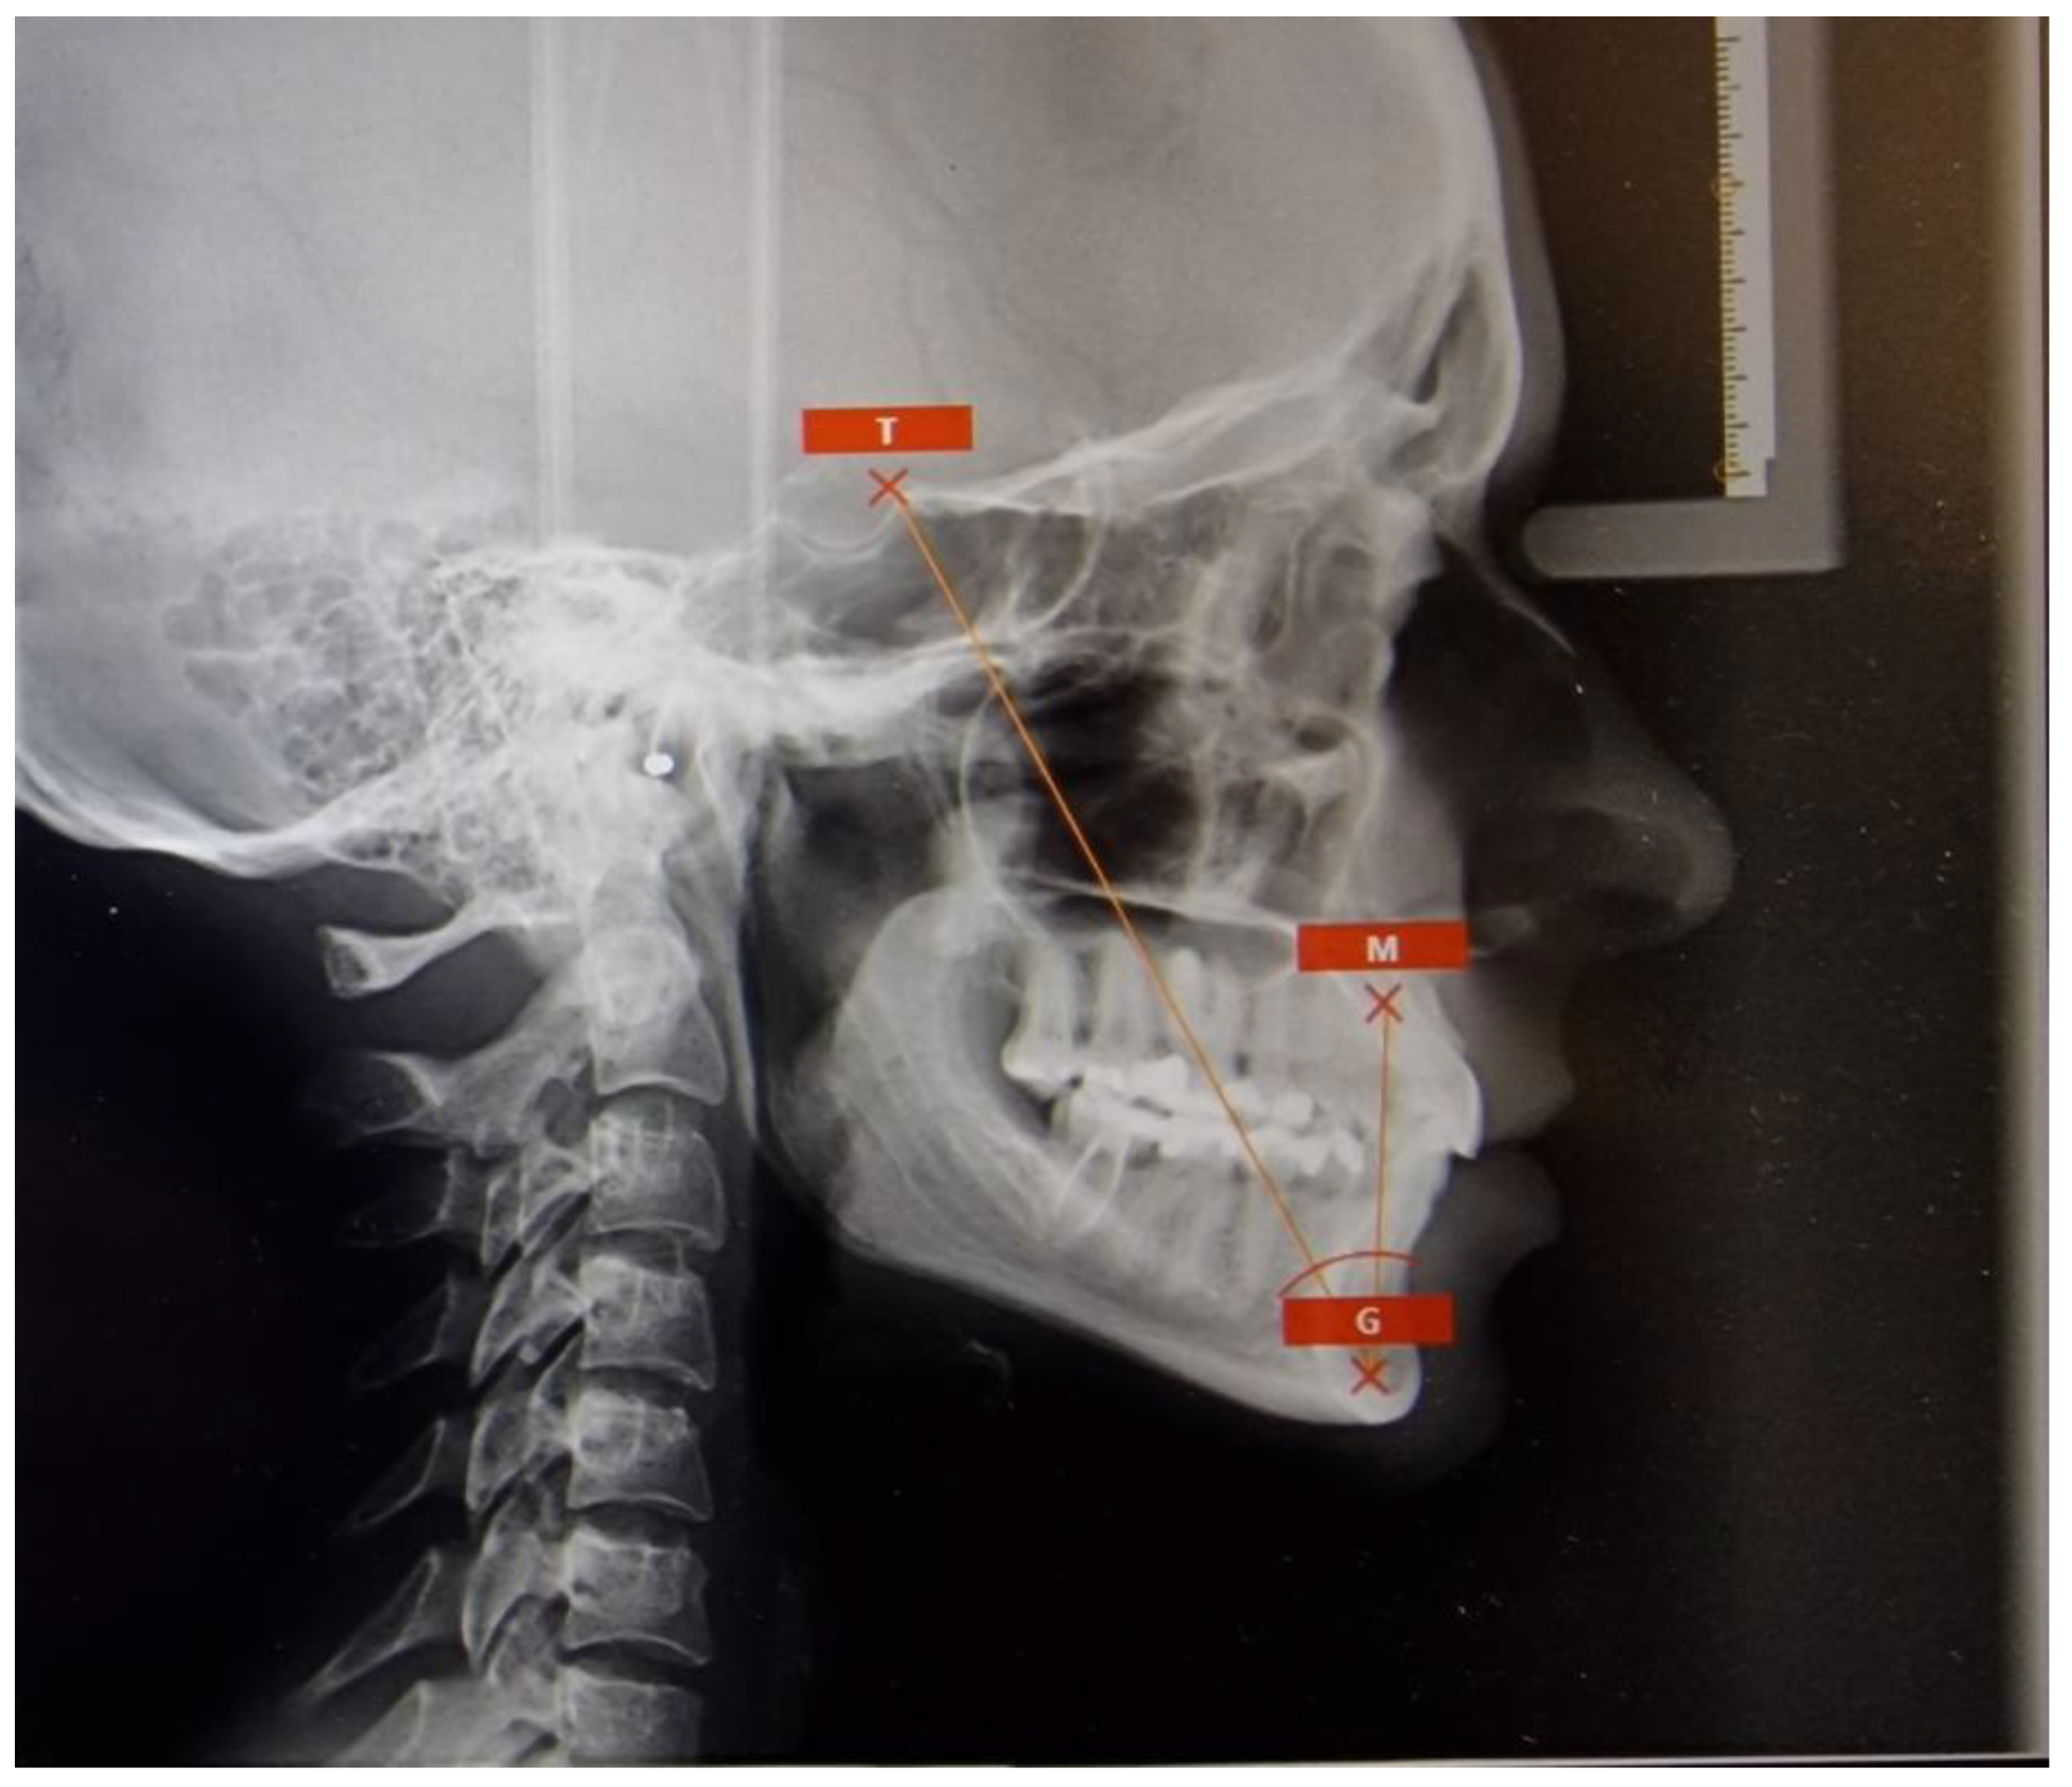

- YEN angle assessment [9] is based on landmarks such as S, M (midpoint of the anterior maxilla), and G (center at the bottom of the symphysis), which together form the YEN angle measured at point M. Points M and G are the same as those used in Tau angle analysis. The imprecision arises from the fact that point G shifts in a manner resembling the letter ‘S’ during growth.